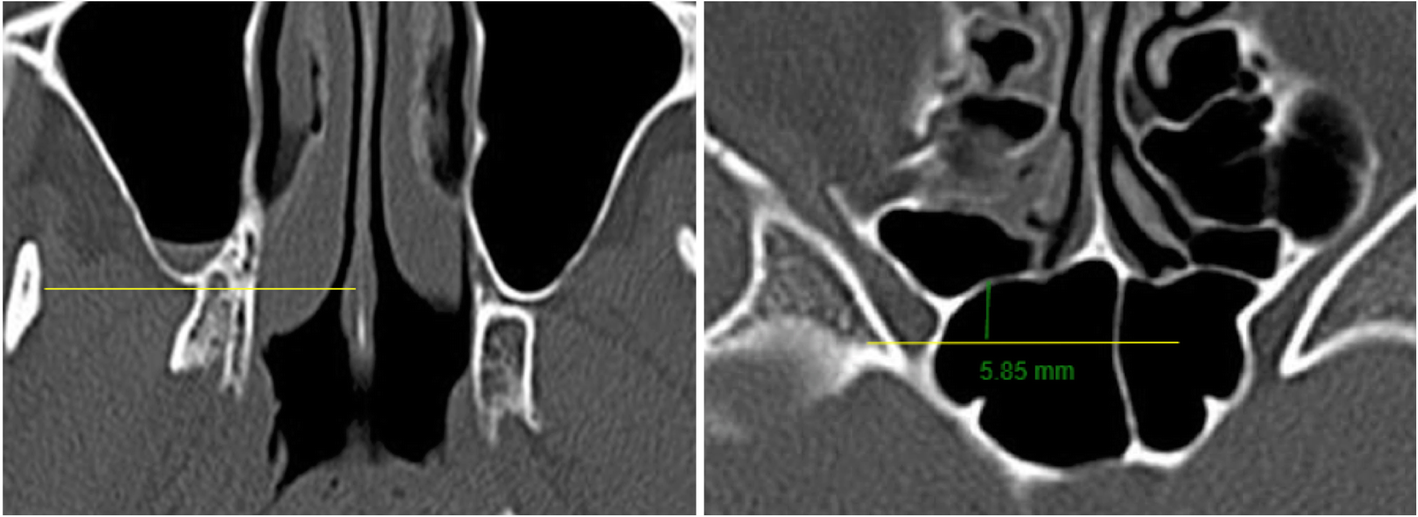

Fig. 8

From: Ethnic variation in medial orbital wall anatomy and its implications for decompression surgery

Relative position of posterior ethmoid sinus to posterior maxillary wall. Using the slide where the posterior maxillary wall is at its most posterior position, a horizontal line is drawn (yellow). A vertical line (green) is then drawn and measured from this horizontal line to the most posterior aspect of ethmoidal sinus. A positive value was given if the posterior maxillary wall lay anterior to the posterior ethmoidal wall. A negative value was given if the posterior maxillary sinus wall lay posterior to the posterior ethmoidal wall